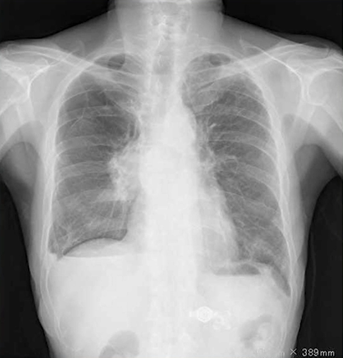

先端巨大症:糖尿病性ケトアシドーシスがきっかけで診断された症例ですが、耐糖能異常や血圧高値と顔貌から疾患を想起します。

34歳男性。糖尿病性ケトアシドーシス(DKA)で入院してきたところ、「顔が特徴的(広がった鼻・前頭部の隆起・突出した下顎・上切歯の不整咬合)」であることに代謝内…